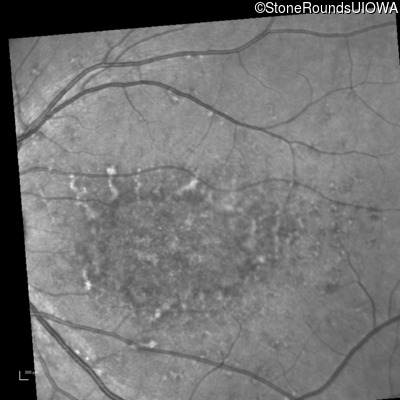

Blue Autofluorescence - Right - 20/125 -1

Exemplar